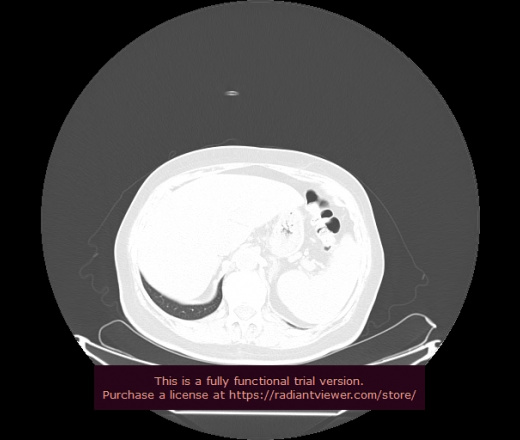

Уважаемые коллеги, если имеется интерес, сможете ли Вы спрогнозировать дальнейшее +-одинаковое течение процесса у 4 данных разных пациентов? Зацепиться где-то можно очень просто, где-то нельзя.